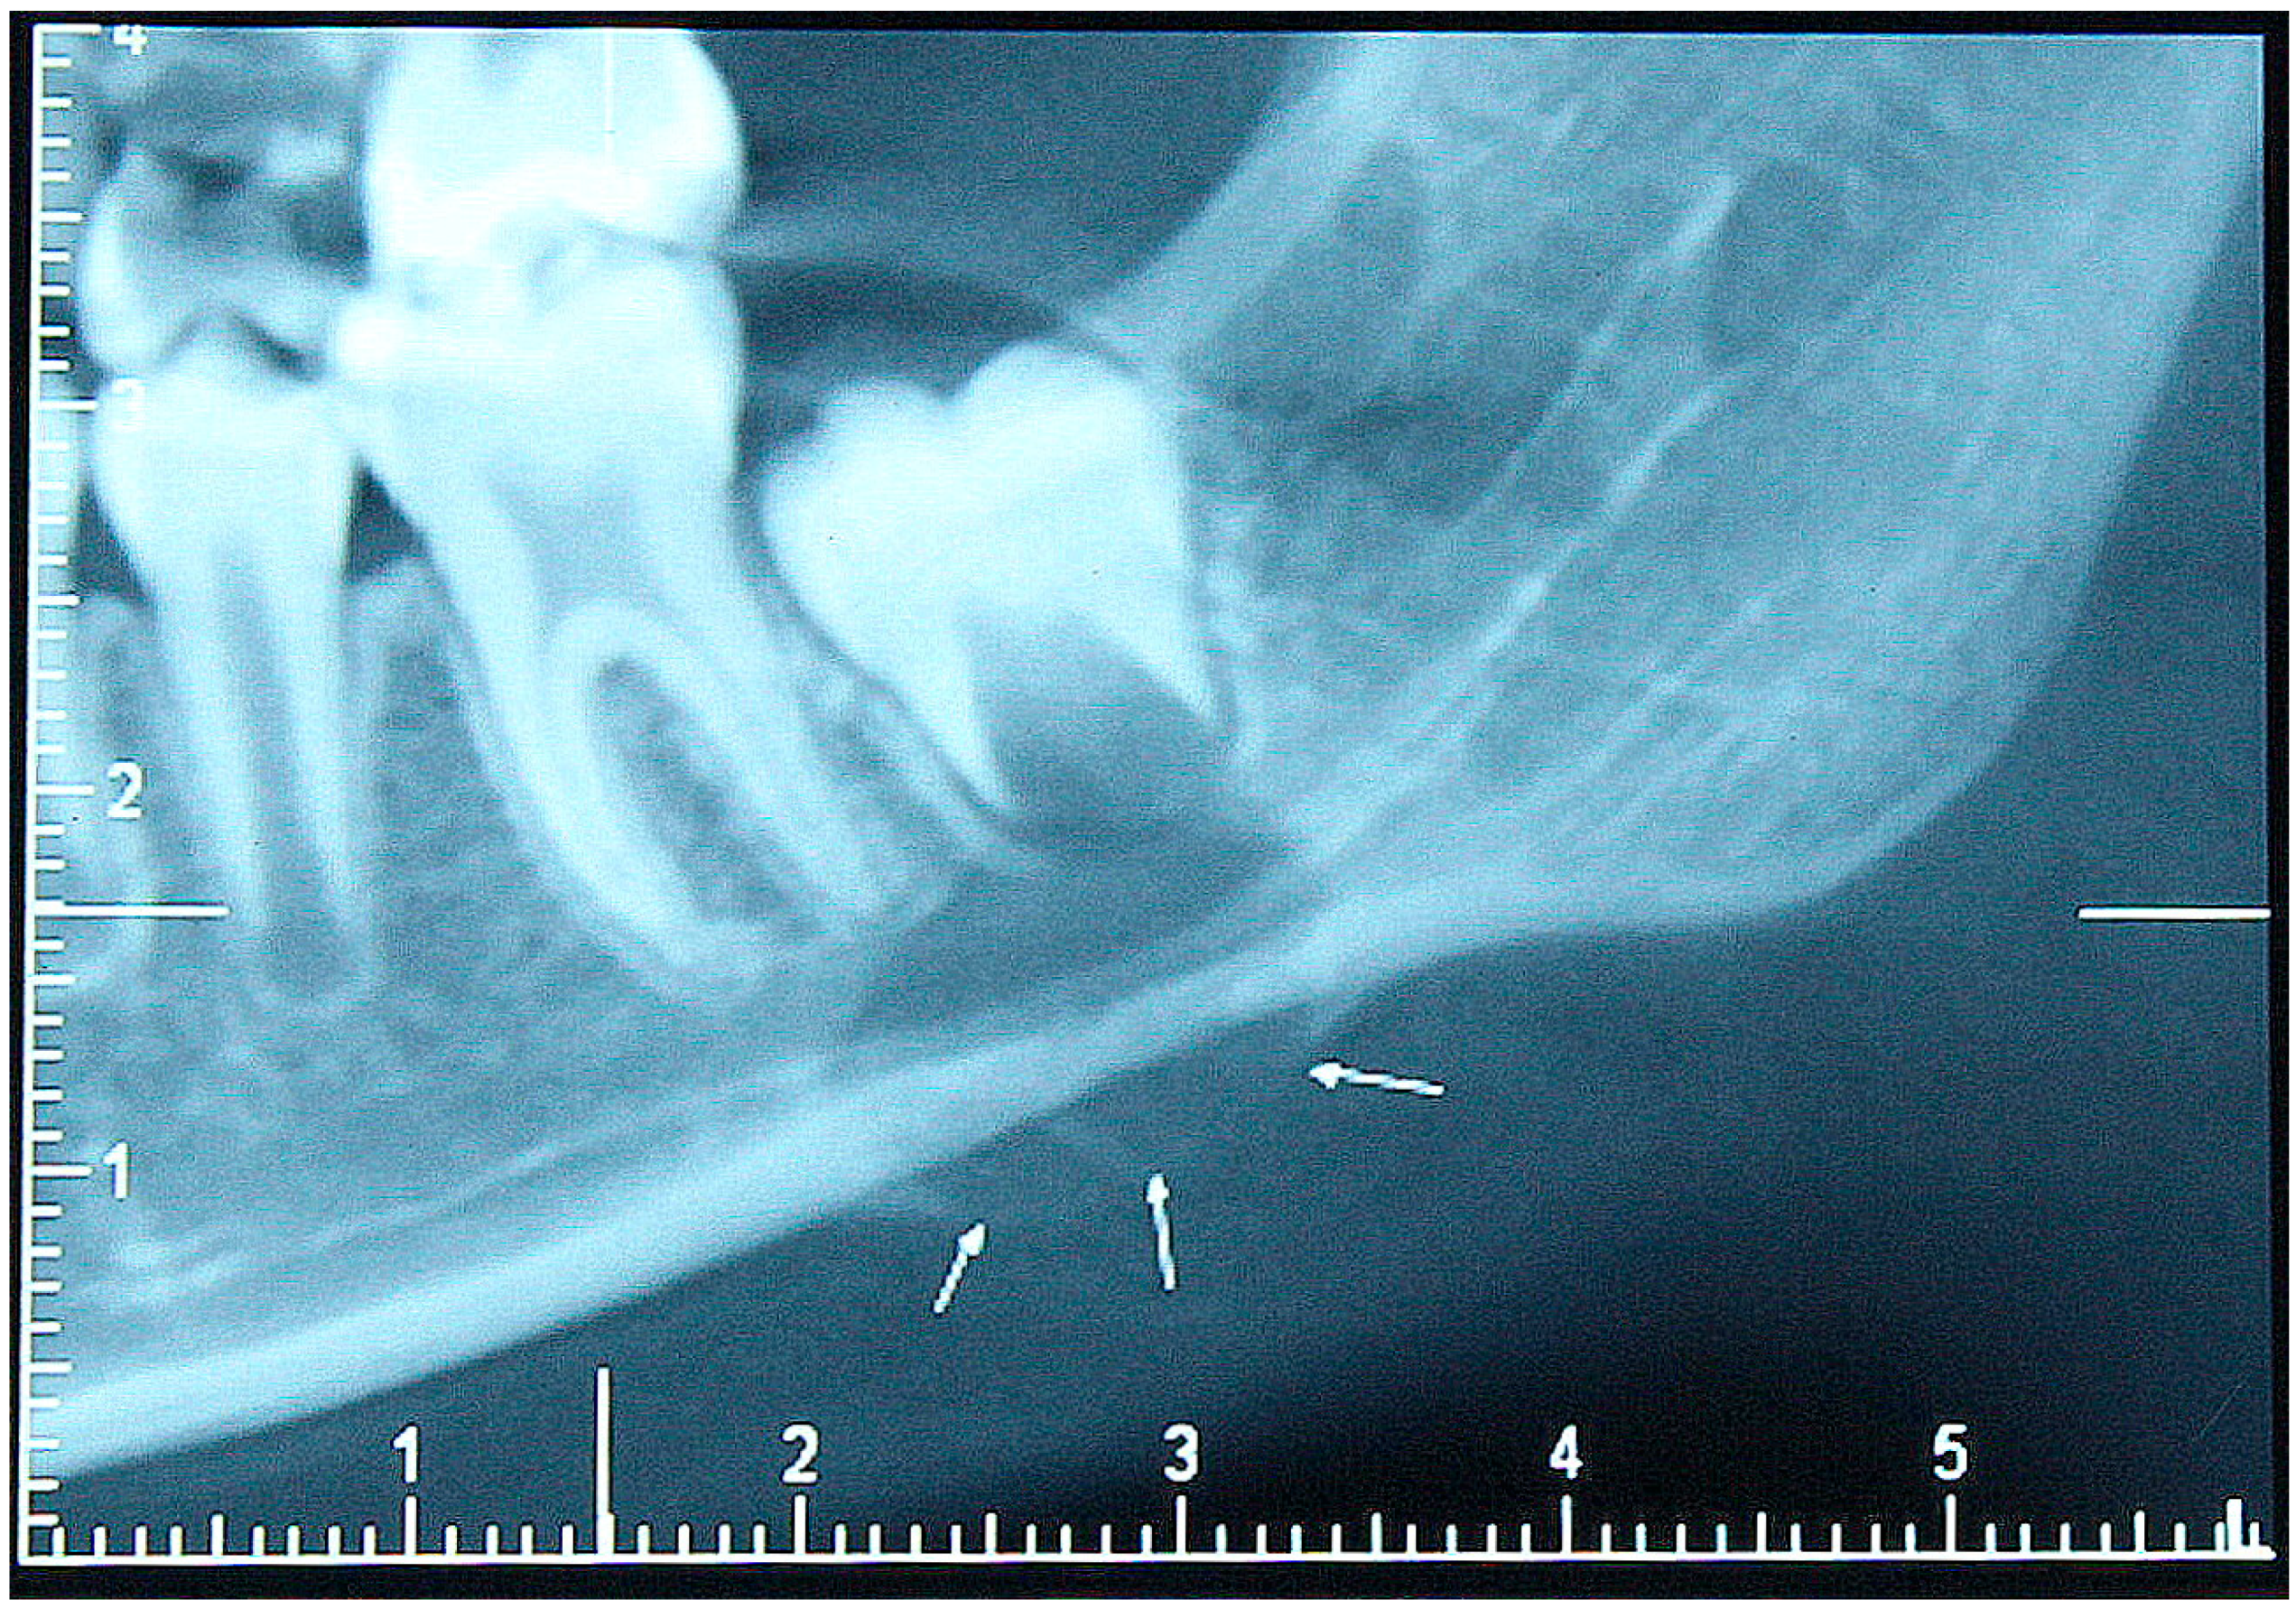

2. Patient Description